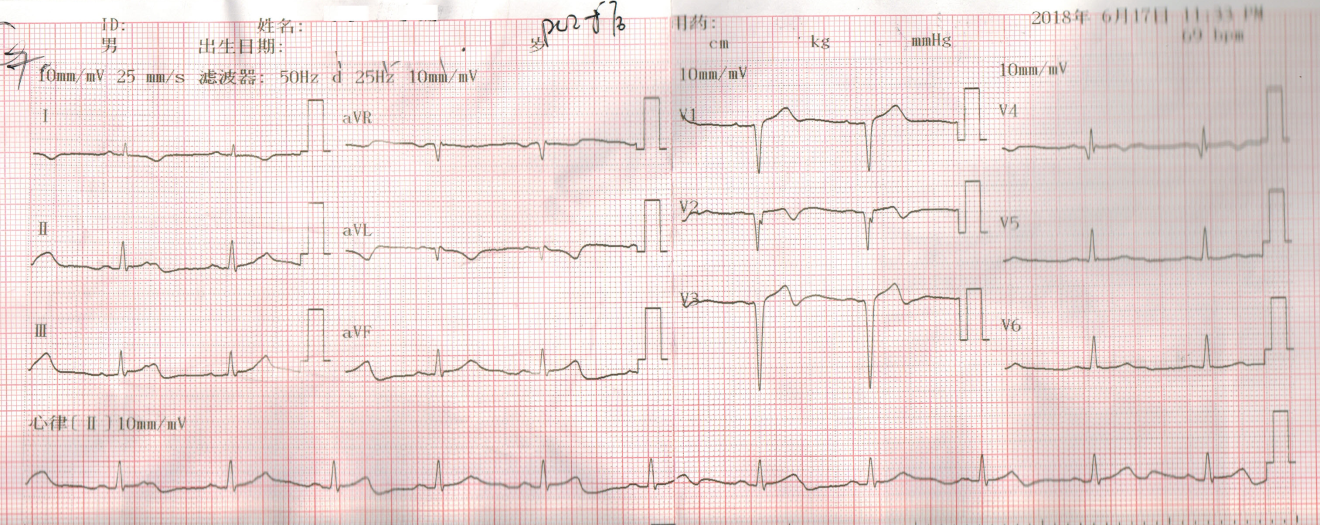

2 结果 本研究收集7例De winter综合征患者,6例进行了急诊冠脉造影,胸痛至球囊扩张平均时间为3.3 h,1例进行择期冠脉造影。其中,3例为前降支近段严重病变,1例为第一对角支闭塞,3例为前降支中段闭塞,2例合并多支血管病变,5例为单支血管病变,均行前降支支架植入术(表 4)。1周内行心脏彩超检查,4例出现室壁运动减弱,2例EF值小于50%,2例心脏形态结构未见异常,1例患者术后第2天因个人原因自动出院,未完善心脏彩超(表 5)。观察7例患者住院期间心电图演变情况,其中有3例在PCI术后出现前壁导联ST段抬高,4例未出现ST段抬高(表 5)。病例1住院期间出现室性心动过速,病例7患在急诊科就诊时发生呼吸心搏骤停,经抢救后送导管室行急诊冠脉造影。另外,所有患者经药物及介入治疗后,均症状缓解出院,院外长期服用阿司匹林100 mg/d+替格瑞洛90 mg/12 h+阿托伐他汀40 mg/瑞舒伐他汀20 mg等药物,出院1个月后电话随访,7例患者均无胸痛、气促发作及再住院,无死亡病例。

表 5 7例患者的心电图演变及心脏彩超结果

| 编号 |

心电图是否演变为ST段抬高 |

心脏彩超 |

| 病例1 |

是(图 3~5) |

左心扩大,左室前间壁、前侧壁及心尖部运动减弱,EF 35% |

否(图 1~2) |

心脏形态结构未见异常,EF 56% |

3 讨论 De winter综合征是近10年来新发现的心电图诊断,其诊断标准为:⑴胸前导联T波高尖对称; ⑵胸前V1-6导联J点压低1~3 mm,ST段呈上斜型下移; ⑶QRS波群通常不增宽或轻度增宽; ⑷可出现胸前导联R波递增不良; 大多数患者aVR导联ST段抬高1~2 mm。当然,这仅是心电图诊断,具体还要结合临床及其他辅助检查。目前其已被证实与前降支急性闭塞有关,占急性前壁心肌梗死的2%。虽然De winter综合征不属于STEMI范畴,但因其心血管事件的发生风险较高,有学者提出,其治疗时机应参照STEMI,尽早行冠脉造影及干预靶血管,改善预后。本文7例De winter综合征病例中,6例患者行急诊冠脉造影+PCI术,术后心脏彩超证实4例患者心功能恢复良好,1例(病例1)心脏收缩功能受到影响(EF 35%),恰巧该患者PCI术后心电图也演变为STEMI,是否演变为STEMI的De winter综合征患者的心功能较未演变为STEMI的患者更容易受损,有待于进一步证实。1例(病例5)择期冠脉造影+PCI术患者心功能明显受损,这可能与缺血时间长,心肌细胞损伤严重有关。另外,住院期间心血管事件发生、30 d再住院、死亡等方面,7例患者预后均良好。

De winter综合征的主要心电图改变为:胸前V1-V6导联ST段呈上斜型下移,T波对称高尖,多数患者aVR导联ST段轻度上抬。出现这种心电图改变的原因尚未清楚。传统观点认为ST段压低,是因为心肌细胞受损后,由于不能正常除、复极,导致正常与异常心肌细胞之间产生电位差,出现损伤电流,导致ST段出现了相对或直接偏移。近年来,有人提出离子流学说,正常时Ito电流分布为外膜>内膜,当心内膜心肌缺血时,内膜Ito电流明显增大,达到钙失活电位后,造成二相平台丢失,内外膜之间形成的电位差由高到低指向心内膜,背离探查电极,从而引起ST段压低[5]。刘元生[6]则认为,前壁导联ST段未抬高,可能与细胞膜上ATP敏感性钾通道(KATP)不能激活有关,其机制是心肌缺血使ATP产生缺乏。也有学者推测可能是反复心肌缺血,及各冠脉之间已形成广泛的侧支循环所致[7]。

De winter综合征表现为T波高尖,临床上应注意与急性心肌梗死超急性期、高钾等疾病相鉴别。有学者认为,De winter综合征不会演变成STEMI,与STEMI超急性期的鉴别关键在于密切监测心电图,如果是De winter综合征,其ST段不会抬高,而急性心肌梗死超急性期心电图会有动态演变,T波高尖之后会逐渐出现ST段抬高,R波下降甚至丢失,病理性Q波形成等特点,但这种观点与本研究观察到的情况不符,本文中病例1、病例5和病例6都观察到心电图演变为STEMI。临床上观察不到的原因可能是:⑴患者发病时间短,心电图还来不及演变为ST段抬高,就已行冠脉造影及支架植入开通血管。⑵ST段抬高可能是一过性的,开通血管后ST段又回落至基线。只有密切监测心电图,才可能真正发现问题。至于与高钾导致的T波高尖的鉴别,急查血清钾即可明确。De winter等[1]发现心电图表现为ST段上斜型压低,T波高尖的患者,冠脉造影均提示前降支近段闭塞,且为单支血管病变。本文中观察到,3例为前降支近段严重病变,1例为第一对角支闭塞,3例为前降支中段闭塞,2例合并多支血管病变,5例为单支血管病变。亦有研究发现,心电图表现为De winter综合征,但冠脉造影却提示左主干闭塞[8]。可见,本文的发现及Murat等[8]的发现提示De winter综合征的靶病变不一定局限于LAD近段。另外,从本文观察到的情况,患者发病年龄都相对年轻,且均为男性,2例合并高脂血症,与以往文献报道[9]相符。